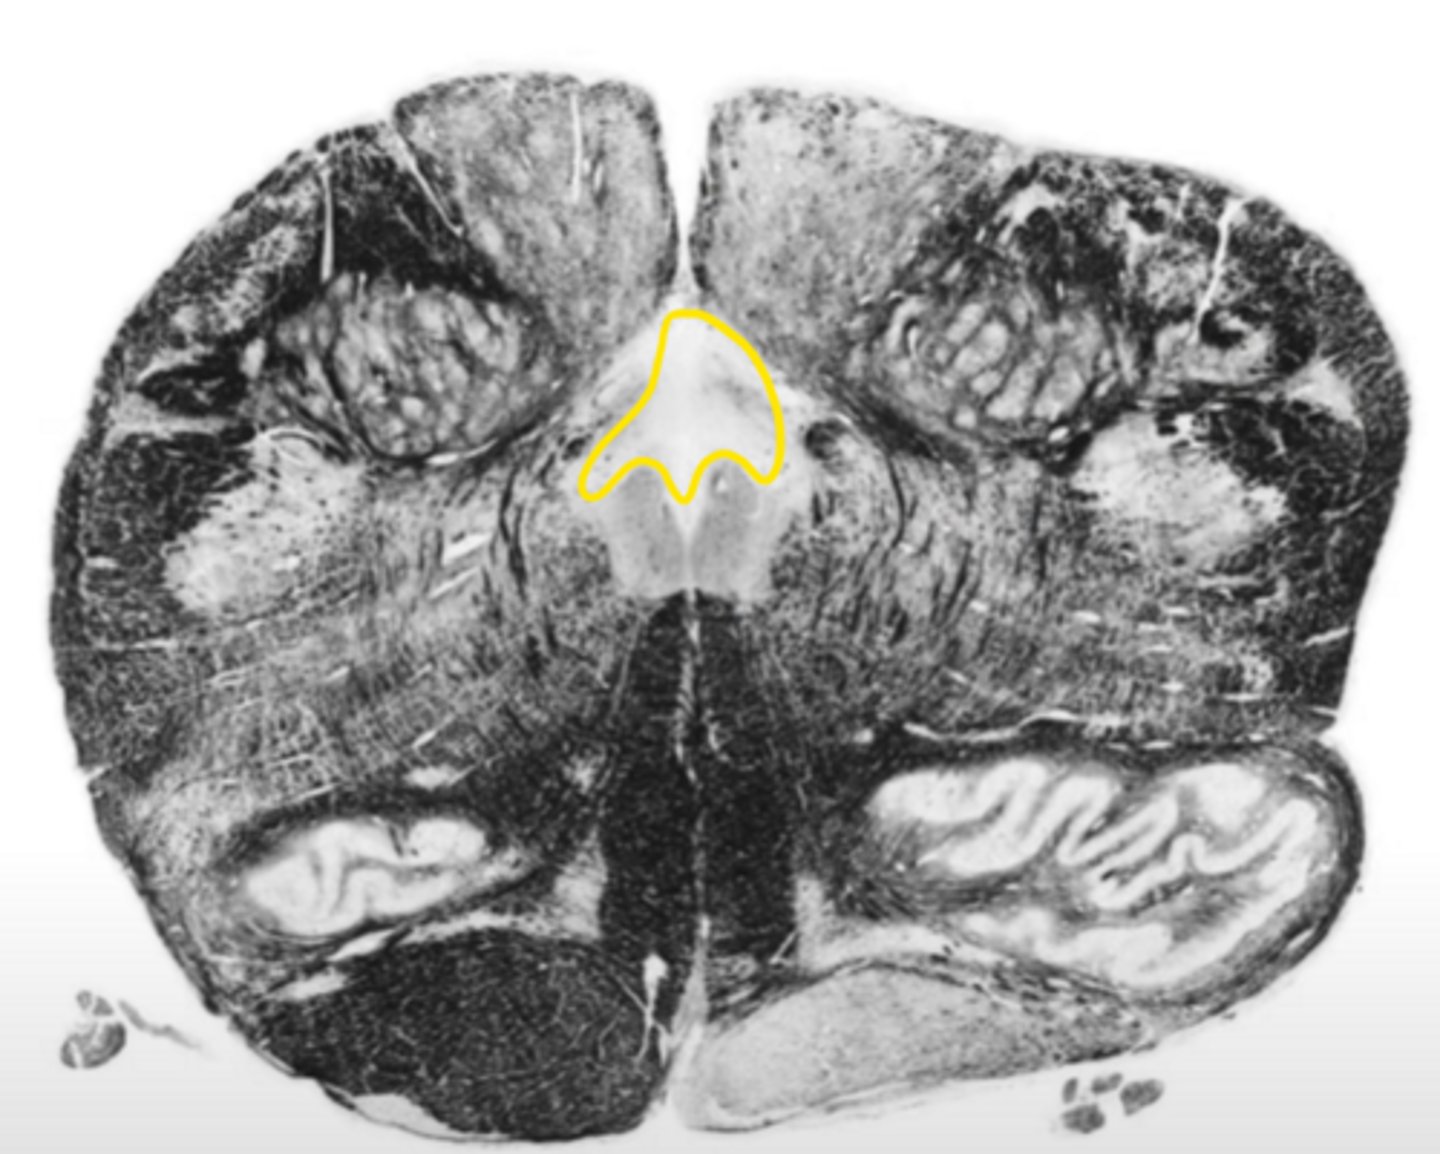

posterior median sulcus

ID the structure

hypoglossal nucleus

ID the nucleus

central gray

gracile nucleus

posterior intermediate sulcus

cuneate nucleus

ID the light area

cuneate fasciculus

ID the dark area

internal arcuate fibers

medial lemniscus

principle olivary nucleus

corticospinal fibers

anterior median sulcus

gracile fasciculus

posterior lateral sulcus